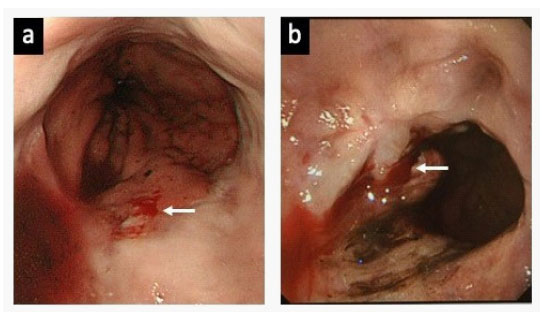

Figure 2: 2nd and 5th emergent endoscopic therapies

a. The blood oozing (white arrow) was found near the gastroesophageal junction at the time of 2nd emergency endoscopy.

b. Active bleeding (white arrow) was detected at the time of 5th emergency endoscopy. However, telangiectasia could not be obviously demonstrated.